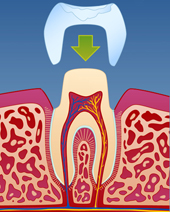

Ved langvarig og alvorlig tanngnissing, kan tennene etter hvert bli svært slitt. Dette kan gå ut over både tennenes funksjon og utseende. I slike tilfeller kan det være nødvendig å bygge opp igjen tennene enten ved hjelp av plastfyllinger eller med kroner i porselen (fig. V-VIII). Dette kan være kostbar og omfattende behandling og kan i enkelte tilfeller utløse støtte fra Helfo. Det er tannlegen som vurderer om tilstanden er så alvorlig at den omfattes av dette regelverket.

| figur V | | figur VI | | figur VII | | figur VIII |